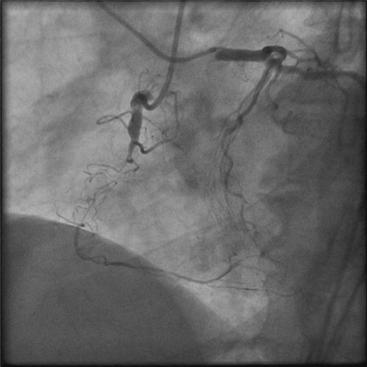

تشخیص قطعی CTO از طریق آنژیوگرافی عروق کرونر انجام میشود.

در آنژیوگرافی مشخص میشود:

باز کردن CTO نیازمند تکنیکهای پیشرفته و ابزارهای خاص است که بسته به آناتومی رگ انتخاب میشوند:

در نهایت، پس از عبور موفق، آنژیوپلاستی و استنتگذاری انجام میشود.